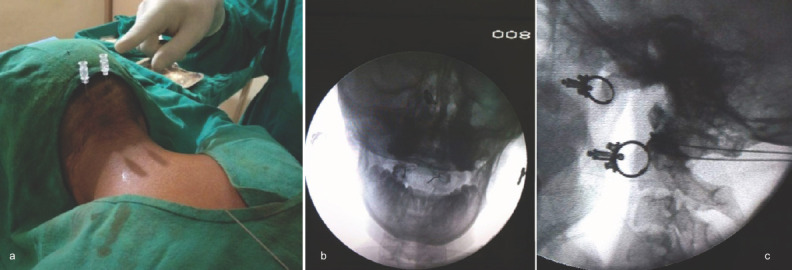

Patient positioning for atlantoaxial joint injection with bilateral spinal needles visible on AP and lateral fluoroscopic views.

1. Patient positioning: Prone or lateral decubitus

2. Imaging guidance: Fluoroscopy (AP and lateral views) or CT guidance

4. Approach: Posterolateral — the needle is advanced to the posterior aspect of the C1-2 joint

Fluoroscopic Target Acquisition:

• To find the posterior joint: decline the fluoroscope until the lucent joint space is lost, then rotate cranially until joint lucency and crisp cortical margins are first acquired — this images the posterior aspect the needle must enter

• True AP is verified by centering the dens within the ring of C1 and ensuring C2 pedicles are equidistant from the spinous process

• Intermittent true lateral views confirm appropriate trajectory and depth